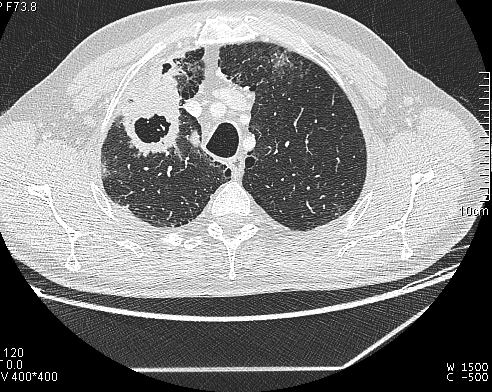

Obtenemos las siguientes imágenes en distintos planos:

Vemos que la estructura cavitada posee una pared muy gruesa, más típica de un proceso neoplásico, y una cavidad hipodensa. Confirmamos su localización en el lóbulo superior derecho y anterior. Descartamos proximidad a vasos y estructuras mediastinicas, así como invasión de la pared torácica. Y lo mas importante es que apreciamos que el bronquio principal mas proximal a la masa cavitada, el bronquio anterior del lóbulo superior derecho, se encuentra amputado cuando llega a la masa y no comunica con la cavidad del interior de la masa,